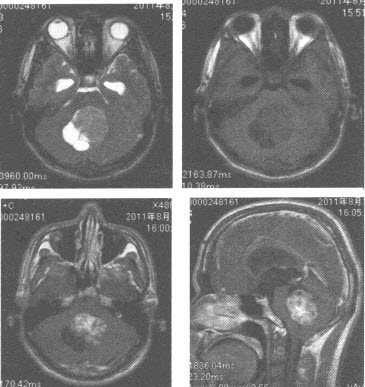

患者,男性,15岁,颅脑MRI平扫及增强扫描图像如下,应诊断为()

A:脑膜瘤

B:胶质瘤

C:小脑母细胞瘤

D:室管膜瘤

E:髓母细胞瘤